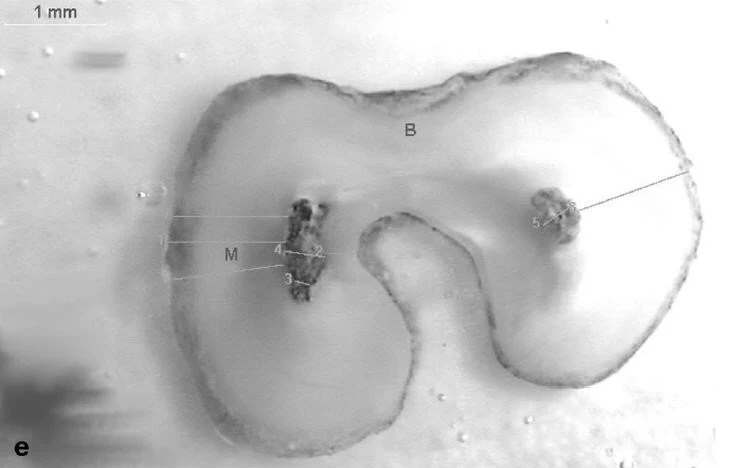

Để OB các răng CS ,lý tưởng nhất là dùng Thermafil cùng với Gutta được làm nóng chảy .

Hình ảnh một ÔT được OB bằng Thermafil+ GP lỏng ( nguồn : GUTMANN).

Kém hơn một chút là dùng cône GT trám và lèn chặt 1/3 chóp rồi bơm GP lỏng vào rồi nhồi xuống,rẻ nhất nhưng cũng khó sử dụng nhất là dùng gutta condensor GC ( dụng cụ quay này có cấu tạo gần như ngược với Hedstrom file ,khi cắm vào tay khoan khuỷu ,quay với vận tốc 30.000 vòng/phút thì nó sẽ làm GP bị nóng chảy và nén xuống ) nhưng sử dụng nó đòi hỏi phải có kinh nghiệm.